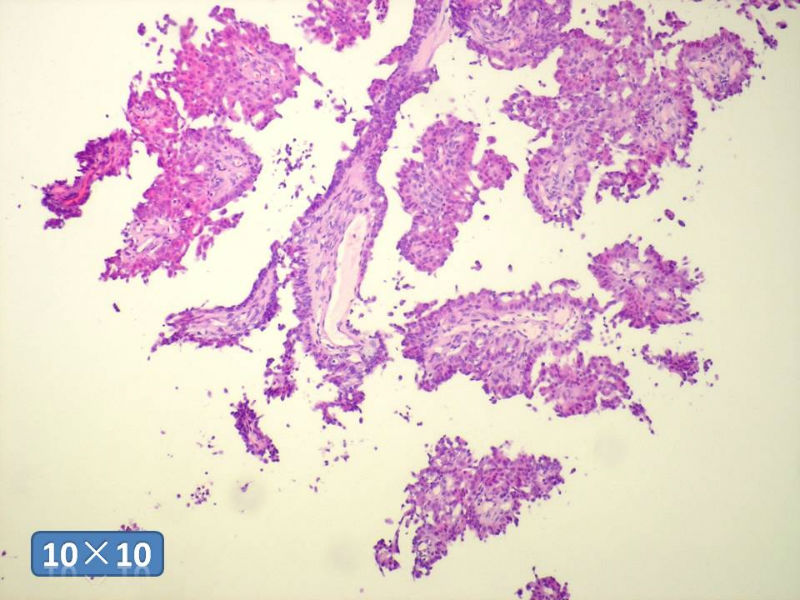

男性,84岁,乳头溢液,流血3个月,送检为乳头内挤出物。

乳腺导管内乳头状瘤

问了病史,确实是乳头导管挤出的组织,免疫做的不是很理想。补充部分HE及免疫结果。